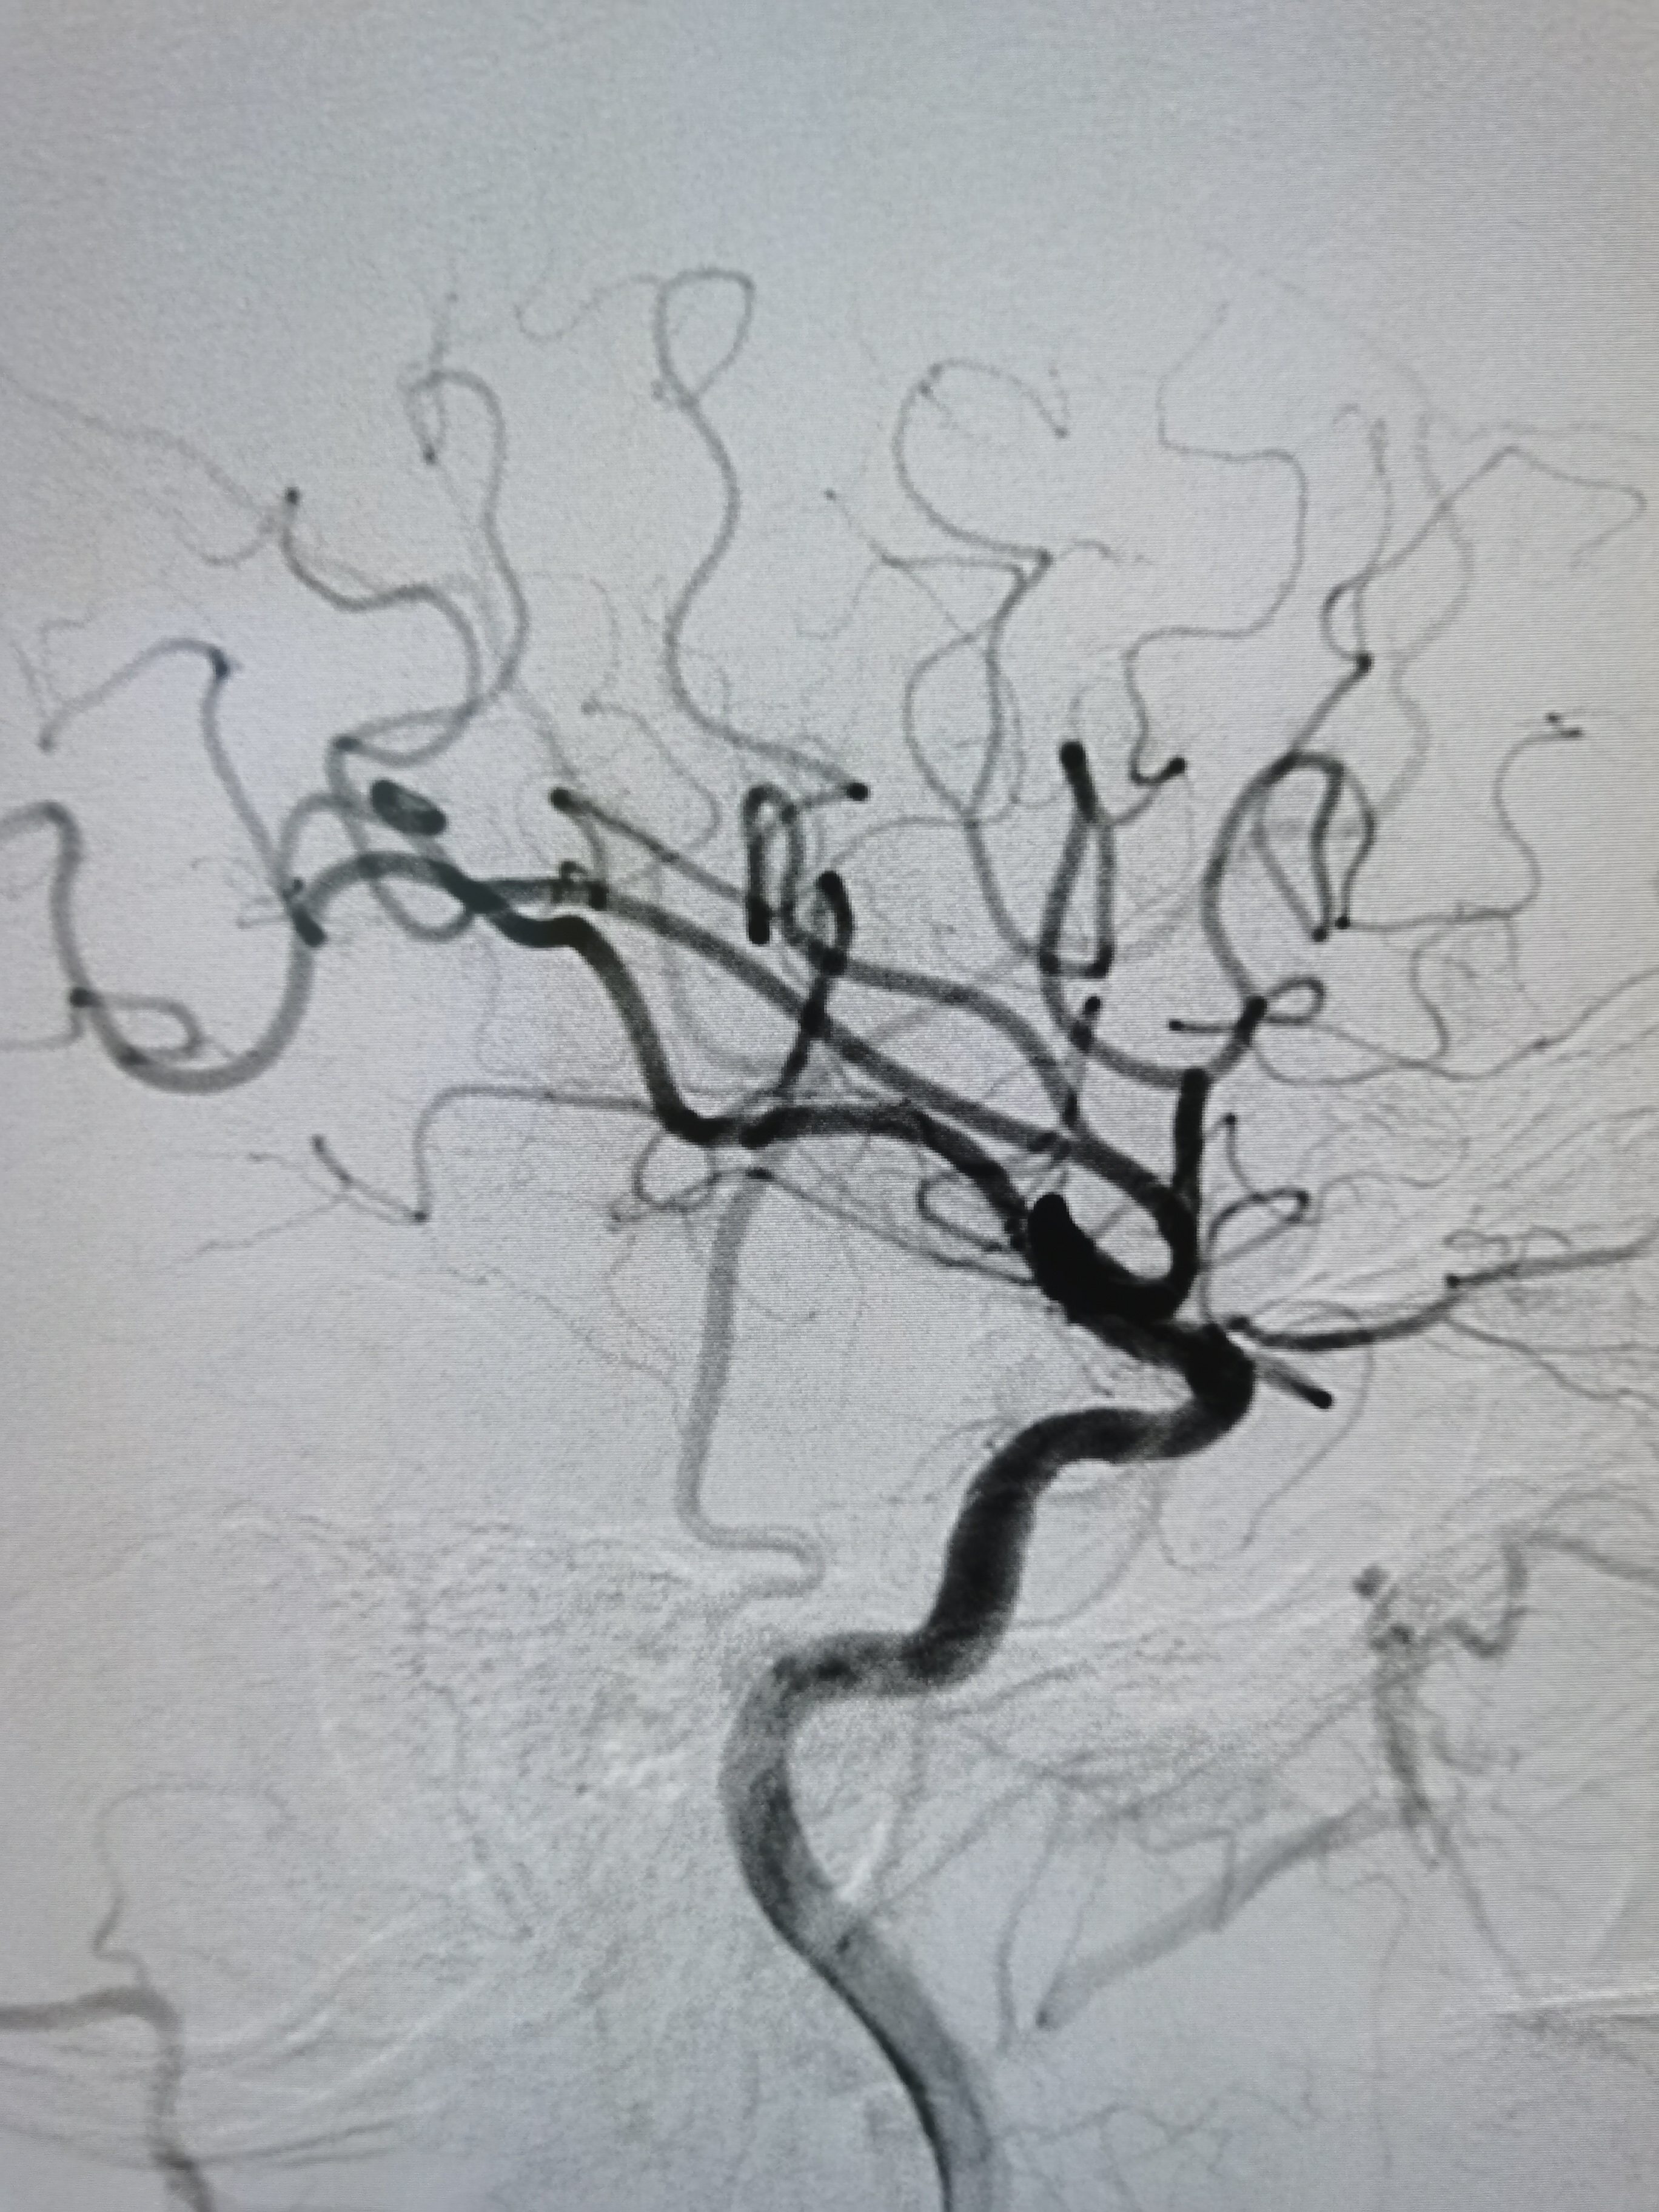

左侧颈内动脉狭窄伴溃疡形成。

颅内段显影可。

双侧大脑前动脉共干。